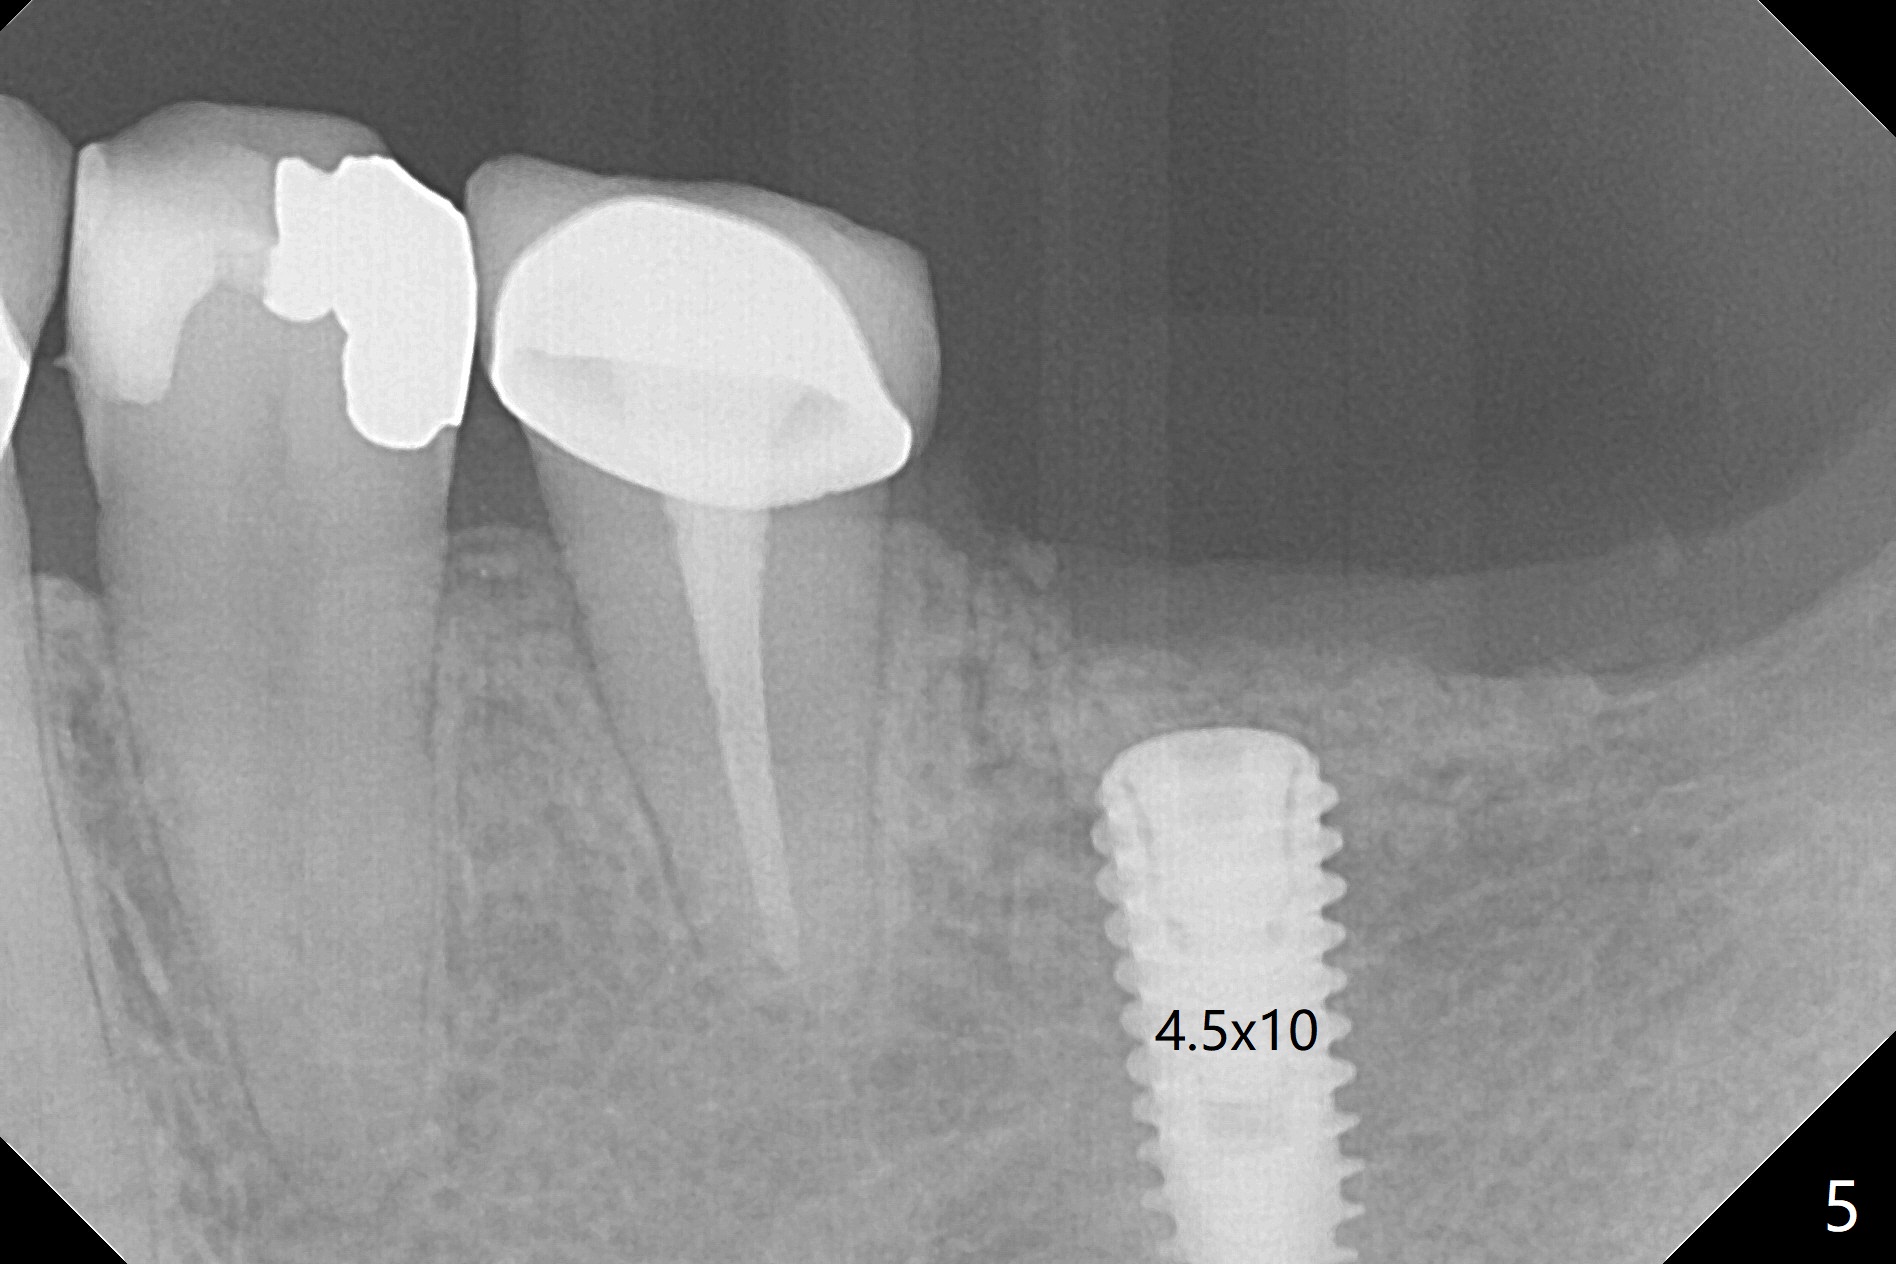

Allograft is placed around the fracture before suturing (Fig.5,6).  To prevent potential buccal plate necrosis, the procedure should be terminated when the ridge is initially split (Fig.3) and restart in 3 weeks.